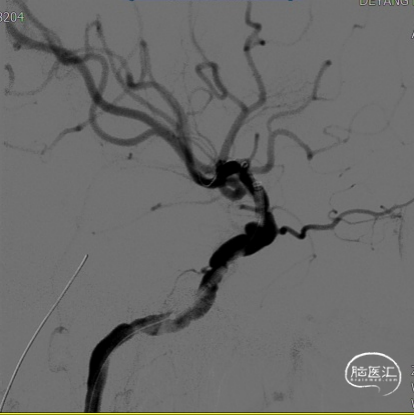

左侧颈内动脉造影提示:左侧颈内动脉C4段多发动脉瘤。大小分别为3.5mm*2.5mm、2.5mm*2.5mm,余各血管及其分支血管走形正常,动脉期、毛细血管期、静脉期均未见异常血管病变,脑循环时间正常。

2. 术前全脑血管造影提示:左侧颈内动脉C4段多发动脉瘤;

(A)

(B)

(C)

A:支架到位前造影确定动脉瘤位置以及拟释放支架位置;B:支架到位;C:支架到位后再次确定支架与动脉瘤位置关系。